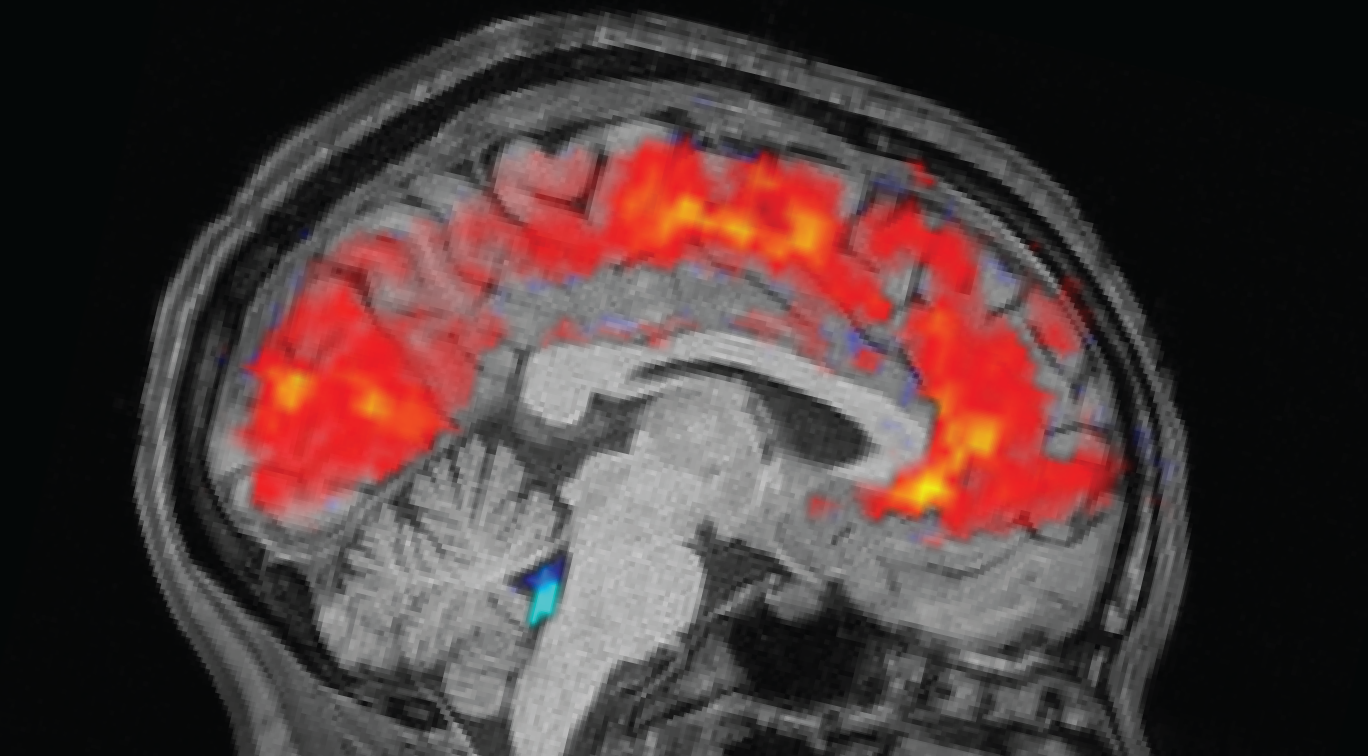

The rested people slept between 6.5 and 9 hours at home, while the sleep-deprived people stayed up all night in the lab. The morning before each experiment, the team fitted participants with electroencephalogram (EEG) caps and recorded their brain waves with electrodes. At the same time, participants underwent functional MRI (fMRI) scans to reveal patterns of blood and CSF flow in the brain. An eye tracker measured the participants’ pupil size.

As expected, participants took longer to notice the stimuli when they were tired and missed cues more often than when they were well-rested. However, the researchers were surprised to see huge CSF pulsations and slow brain wave patterns in the exhausted people. Both are normally observed during non-REM sleep.

Specifically, this pattern was similar to that seen as humans transition from stage N1 to stage N2, the first two of the three stages of non-REM sleep that people experience during each sleep period. “This has previously only been seen at this scale during sleep,” Lewis said.